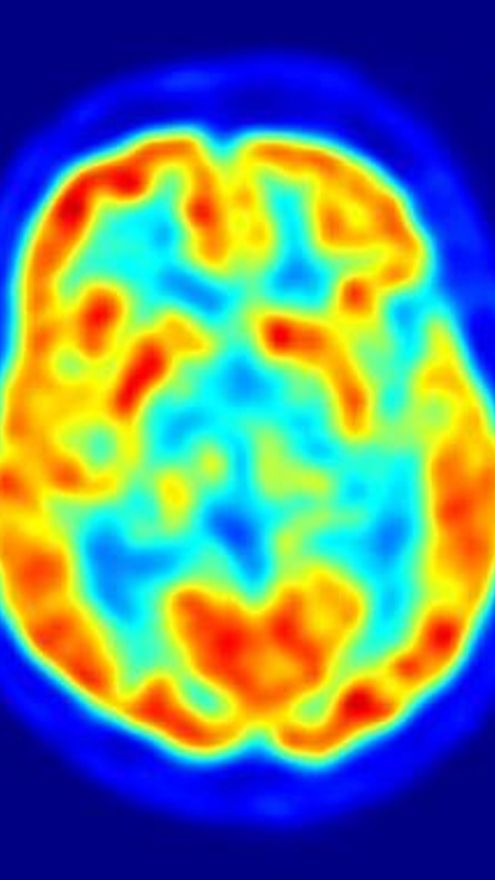

En el estudio, publicado en la revista 'PLoS Biology', el sentido de justicia de los individuos se desafiaba con un juego de justicia monetaria de dos jugadores y su actividad cerebral era medida de forma simultánea utilizando imágenes de resonancia magnética funcional (IRMf).

Investigaciones previas han sugerido que el área que controla la capacidad para analizar y realizar decisiones financieras se localiza en la corteza prefrontal y la ínsula. Utilizando las imágenes de IRMf, sin embargo, los investigadores vieron el área del cerebro que controla las decisiones financieras rápidas se localizaba en realidad en la amígdala, una parte evolutivamente muy antigua y primitiva del cerebro que controla sentimientos de ira y miedo.

Para explorar estos resultados en mayor profundidad, a los individuos se les proporcionaba el tranquilizante antiansiedad oxazepam o un placebo mientras jugaban. Los investigadores descubrieron que aquellos que recibían el fármaco mostraban una menor activación de la amígdala y una mayor tendencia a aceptar una distribución injusta del dinero, a pesar del hecho de que cuando se les preguntaba seguían considerando injusta la sugerencia.

En el grupo control, la tendencia a reaccionar de forma agresiva y a castigar al jugador que había sugerido la distribución injusta del dinero se vinculaba directamente con un aumento en la actividad en la amígdala. Se observó una diferencia de género, ya que los hombres respondían de forma más agresiva ante las sugerencias injustas que las mujeres al mostrar una mayor tasa de actividad de la amígdala. La diferencia de género no se descubrió en el grupo que recibió el fármaco oxazepam.